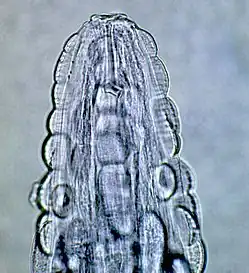

Male Gongylonema pulchrum as seen under a light microscope.[1]

The morphology of the worm is as follows, from a 2000 Veterinary Medicine study: "The anterior end in both sexes was covered by numerous cuticular platelets. There was a pair of lateral cervical papillae. The buccal opening was small and extended in the dorsoventral direction. Around the mouth a cuticular elevation enclosed the labia, and eight papillae were located laterodorsally and lateroventrally. Two large lateral amphids were seen. On the lateral sides of the female's tail, phasmidal apertures were observed. The caudal end of the male was asymmetrically alate and bore 10 pairs of papillae and two phasmidal apertures."[3] The average length for male worms is 29.1 mm (1.15 in), while the average length for adult females is 58.7 mm (2.31 in). The worm is highly mobile, as observed in patients’ mouths and as evidenced by the morphological design of the worm.

These are all pictures from a single Gongylonema pulchrum male extracted from a man in France.[1]